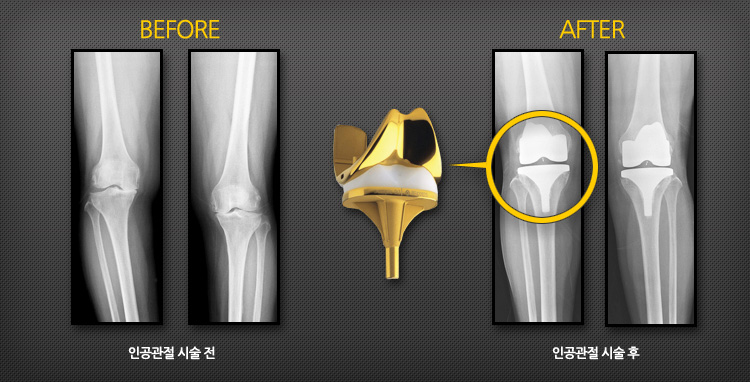

인공 고(엉덩이)관절 전치환술의 증례

인공 고(엉덩이)관절 전치환술후의 효과

특수합금과 고분자 플라스틱 재질로 된 인공 고관절을 삽입하여 통증을 감소시키고 관절운동을 가능하게 하며, 안정성을 얻고 변형을 교정하여 일상생활을 가능하게 해줍니다.